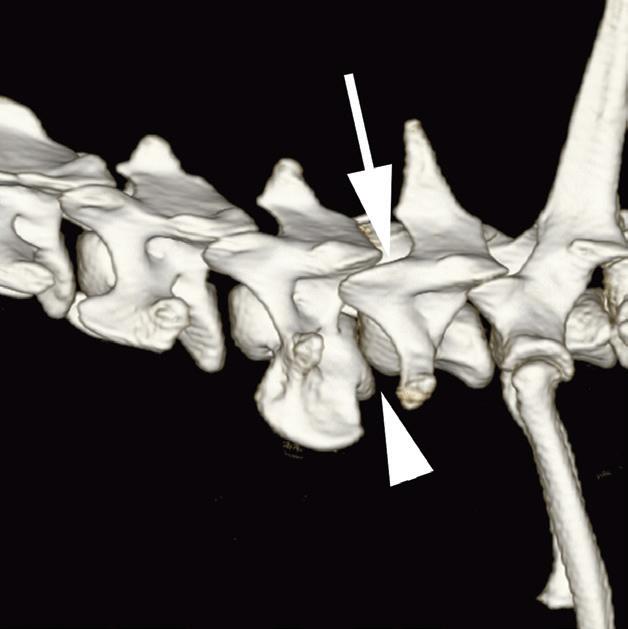

Rycina

3.2.8. Podwichnięcie kręgów szyjnych ze złamaniem wyrostka stawowego (pies) TK i MR

Badania wykonano u 5-letniej samicy mieszańca w typie teriera, która została pogryziona w okolicy szyjnej przez większego psa tego samego dnia, w którym wykonano badania. Podczas wizyty u psa zaobserwowano deficyty neurologiczne z neuroanatomiczną lokalizacją w obrębie C6–T2. Radiogramy przeglądowe ukazały grzbietowe podwichnięcie kręgu C7 względem C6 oraz zwężenie przestrzeni międzykręgowej C6–C7 (a – grot strzałki). Podobne zmiany uwidoczniono na obrazach TK w projekcji strzałkowej i 3D (b, f – grot strzałki). Dodatkowo stwierdzono wieloodłamowe złamanie z przemieszczeniem prawego doczaszkowego wyrostka stawowego kręgu C7 (c–e – strzałka). Dla porównania przedstawiono prawidłowy lewy wyrostek stawowy (f – strzałka). W badaniu MR przestrzeń międzykręgowa C6–C7 była zwężona i wykazywała obniżoną intensywność sygnału w obrazach T2-zależnych (i – strzałka), a przemieszczony materiał dyskowy znajdował się w prawej dobrzusznej części kanału kręgowego (g, h – grot strzałki). W obrazach występują cechy ucisku na rdzeń kręgowy (g–i) oraz zwiększona intensywność sygnału w sekwencji T2-zależnej w obrębie rdzenia na poziomie C6–C7 (h, i), co wskazuje na jego uszkodzenie wewnętrzne. Materiał dyskowy został chirurgicznie usunięty z kanału kręgowego, a podwichnięcie zredukowano i ustabilizowano operacyjnie